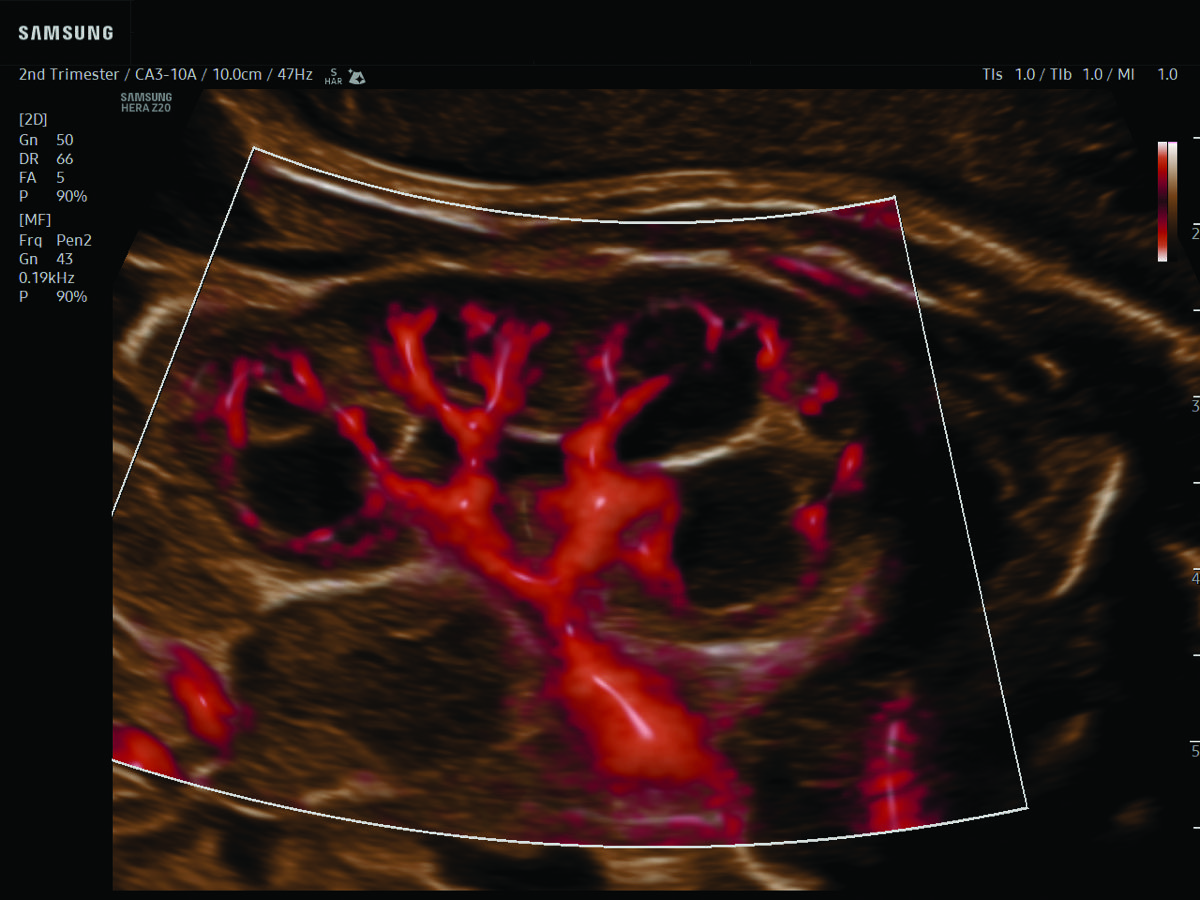

Comprehensive, advanced and expert MFM care for high-risk pregnancies

- Fetal anomalies